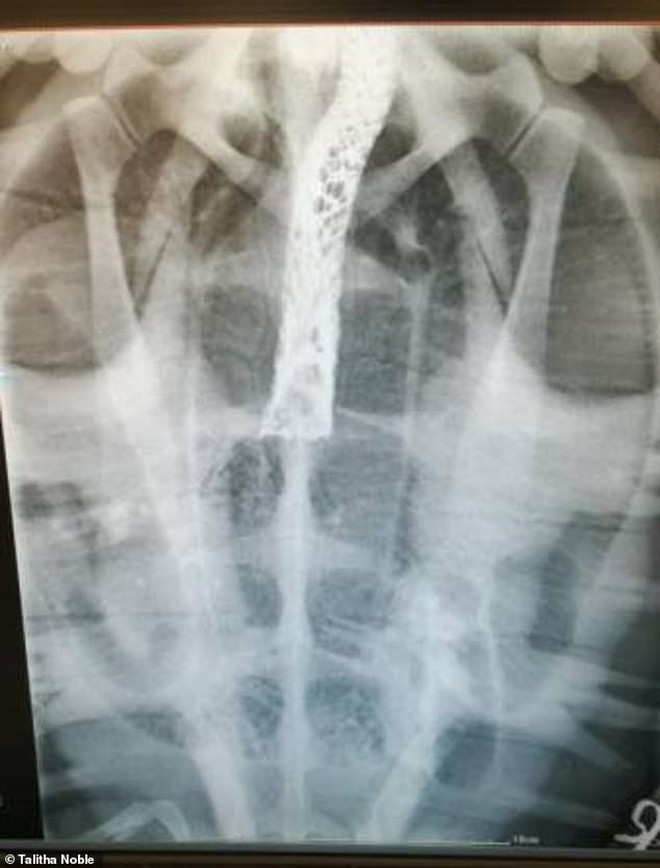

2 chữ "mắc nghẹn" là một khái niệm ẩn dụ, nhưng nó cũng đến từ thực tế. Và bạn sẽ hiểu được trọn cái thực tế ấy qua những gì được tìm thấy trong cổ họng của chú rùa xanh mới dạt vào bờ biển thuộc Cape Town (Nam Phi) thời gian gần đây.

Cụ thể, chú rùa nặng 23kg được tìm thấy trên bờ biển Struisbaai (Cape Town, Nam Phi), trong tình trạng khó thở cực độ. Các chuyên gia sau đó đã đưa chú đến Viện hải dương Two Oceans để thực hiện khám nghiệm.

thầy thuốc Malan van Zyl của viện sau đó đã thực hành chụp X-quang, và lôi ra được 2 dị vật trong khí quản của con rùa.

Nếu vẫn chưa đoán ra chúng là gì, thì bên trái là một đoạn rong biển - thứ chúng vẫn thường ăn. Và bên phải là một dải túi nylon! Theo thông báo, con rùa đã lầm lẫn dải nylon với rong biển, dẫn đến việc bị nghẽn đường thở.

"Trong 10 ngày, con rùa đã trải qua quá nhiều thứ, từ việc dạt vào bờ biển, đến trung tâm hồi sức rồi phải chụp X-quang. Và phải mới đây, chúng ta mới lôi ra được dải túi trong cổ họng của nó."